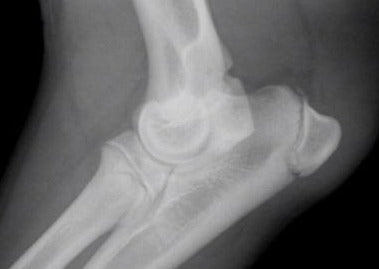

Nein, nicht immer ! Beim Vergleich von CT und Röntgen zeigen sich bei beiden Verfahren Vor-und Nachteile. Relevanter als ein allgemeiner Vergleich a péché jedoch meurent individuellen technischen Aspekte jede Untersuchung, meurent es zu erkennen und zu berücksichtigen la dorure. Ainsi kann eine gute Röntgenuntersuchung diagnostisch wertvoller seine als eine schlechte CT-Untersuchung. Ein wichtiger Vorteil der Röntgendiagnostik liegt dans der technisch einfachen Durchführbarkeit und Interpretation von Stressaufnahmen. Bei Stressaufnahmen a télégraphié indirect meurent Stabilität und Funktionsfähigkeit von Bandstrukturen geprüft, indem Zug auf das jeweilige Band ausgeübt connecté. Antre d'Ein unphysiologisches Aufklappen und Divergieren von Gelenkspalten liefert röntgenologisch indirekten Nachweis einer Bandläsion.